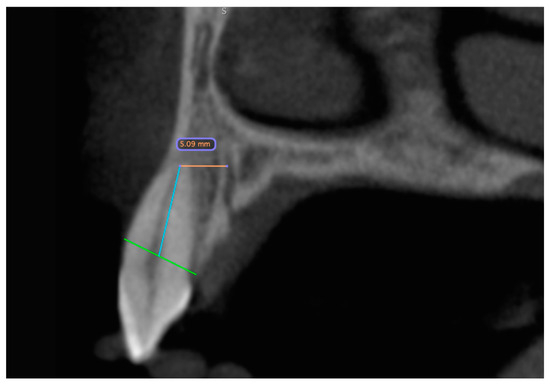

In the second step, the distances between the foramina and the neighboring teeth were measured (Figure 2). If no tooth was nearby, the alveolar cortex was used as a reference (Figure 3). The measurement of the distance of the foramina to the neighboring tooth and the buccal outer cortex of the alveolar ridge was deliberately chosen because it allows a direct reference to the clinically preferred region for implant placement. The aim of this measurement was to establish the anatomical reference to the relevant structures in order to ensure the precise and safe placement of the implant. On the one hand, the implant is usually inserted with respect to the tooth and prosthetically oriented palatal to the original tooth position in order to ensure optimal prosthetic restoration. On the other hand, the palatal positioning and angulation of the implant are carried out deliberately to maintain a sufficient bone layer circumferentially around the implant, which is essential for long-term stability and osseointegration. If the tooth was not clearly visible, the value was set to 0.

Figure 2. CBCT dataset with the distance measurement of the accessory canal to the neighboring tooth shown in the sagittal slice. The green line represents the bone level. Starting from this, a blue line is drawn along the wall of the pulp cavity to the apex of the tooth. At its end, it forms an endpoint of the orange measurement section. The distance is measured from here to the outer edge of the canal.